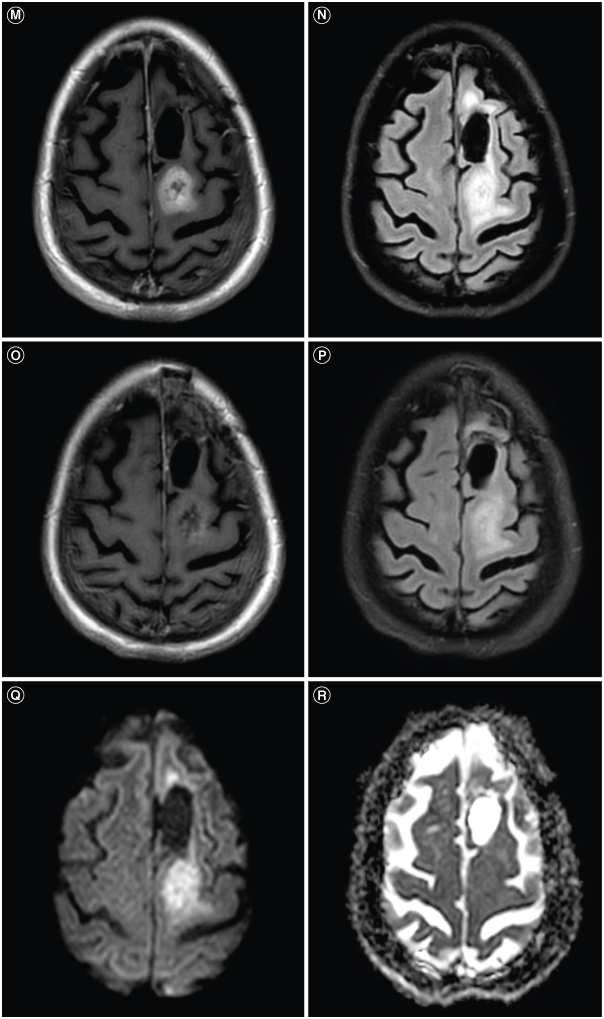

Glioblastoma is the most common malignant primary brain tumor. Despite its infiltrative nature, extra-cranial glioblastoma metastases are rare. We present a case of a 63-year-old woman with metastatic glioblastoma in the lungs. Sarcomatous histology, a reported risk factor for disseminated disease, was found. Genomic alterations of TP53 mutation, TERT mutation, PTEN mutation, and +7/-10 were also uncovered. Early evidence suggests these molecular aberrations are common in metastatic glioblastoma. Treatment with third-line lenvatinib resulted in a mixed response. This case contributes to the growing body of evidence for the role of genomic alterations in predictive risk in metastatic glioblastoma. There remains an unmet need for treatment of metastatic glioblastoma.

Abstract Image